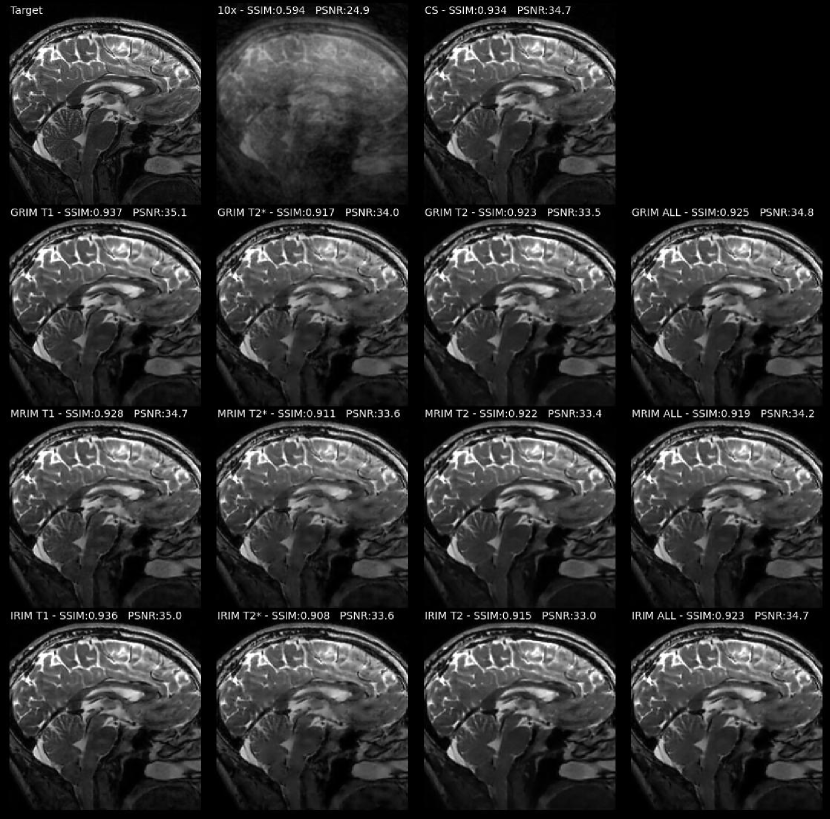

Fig. 5 shows the reconstruction images of one slice from the -weighted TSE brain dataset by each model trained with the -norm as loss function using the different training sets. Observe that the less complex MRIM and IRIM models did not yield degraded image quality compared to the GRIM models. Models trained on the -weighted brain dataset appeared to be affected by residual aliasing noise, resulting in inferior image quality compared to the other models. Example reconstruction of real and imaginary channels of all models and modalities can be found in Suppl. Fig. S1.

3 summarizes the performances of CS and all models trained with the -norm, on the TSE evaluation set. Apparently, the models trained on the -weighted brain data have the highest SSIM scores and are mostly comparable. CS cannot achieve as high PSNR as the RIM models, with any training data.